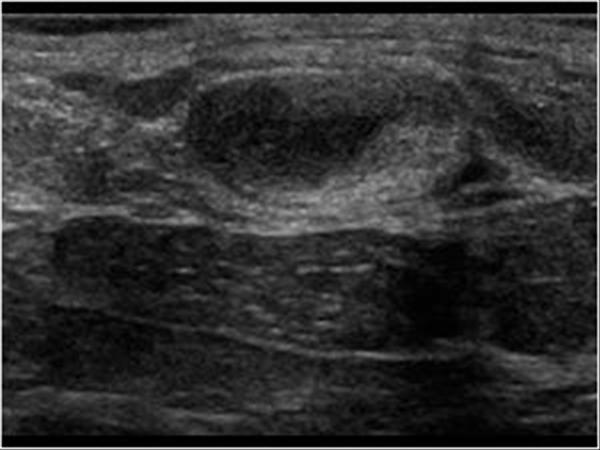

Hoại tử mỡ tuyến vú - Ảnh 3

Hoại tử mỡ tuyến vú

» Thông tin: Nữ giới – 54 tuổi.

» Lâm sàng: Khối tuyến vú / Sau phẫu thuật u vú.